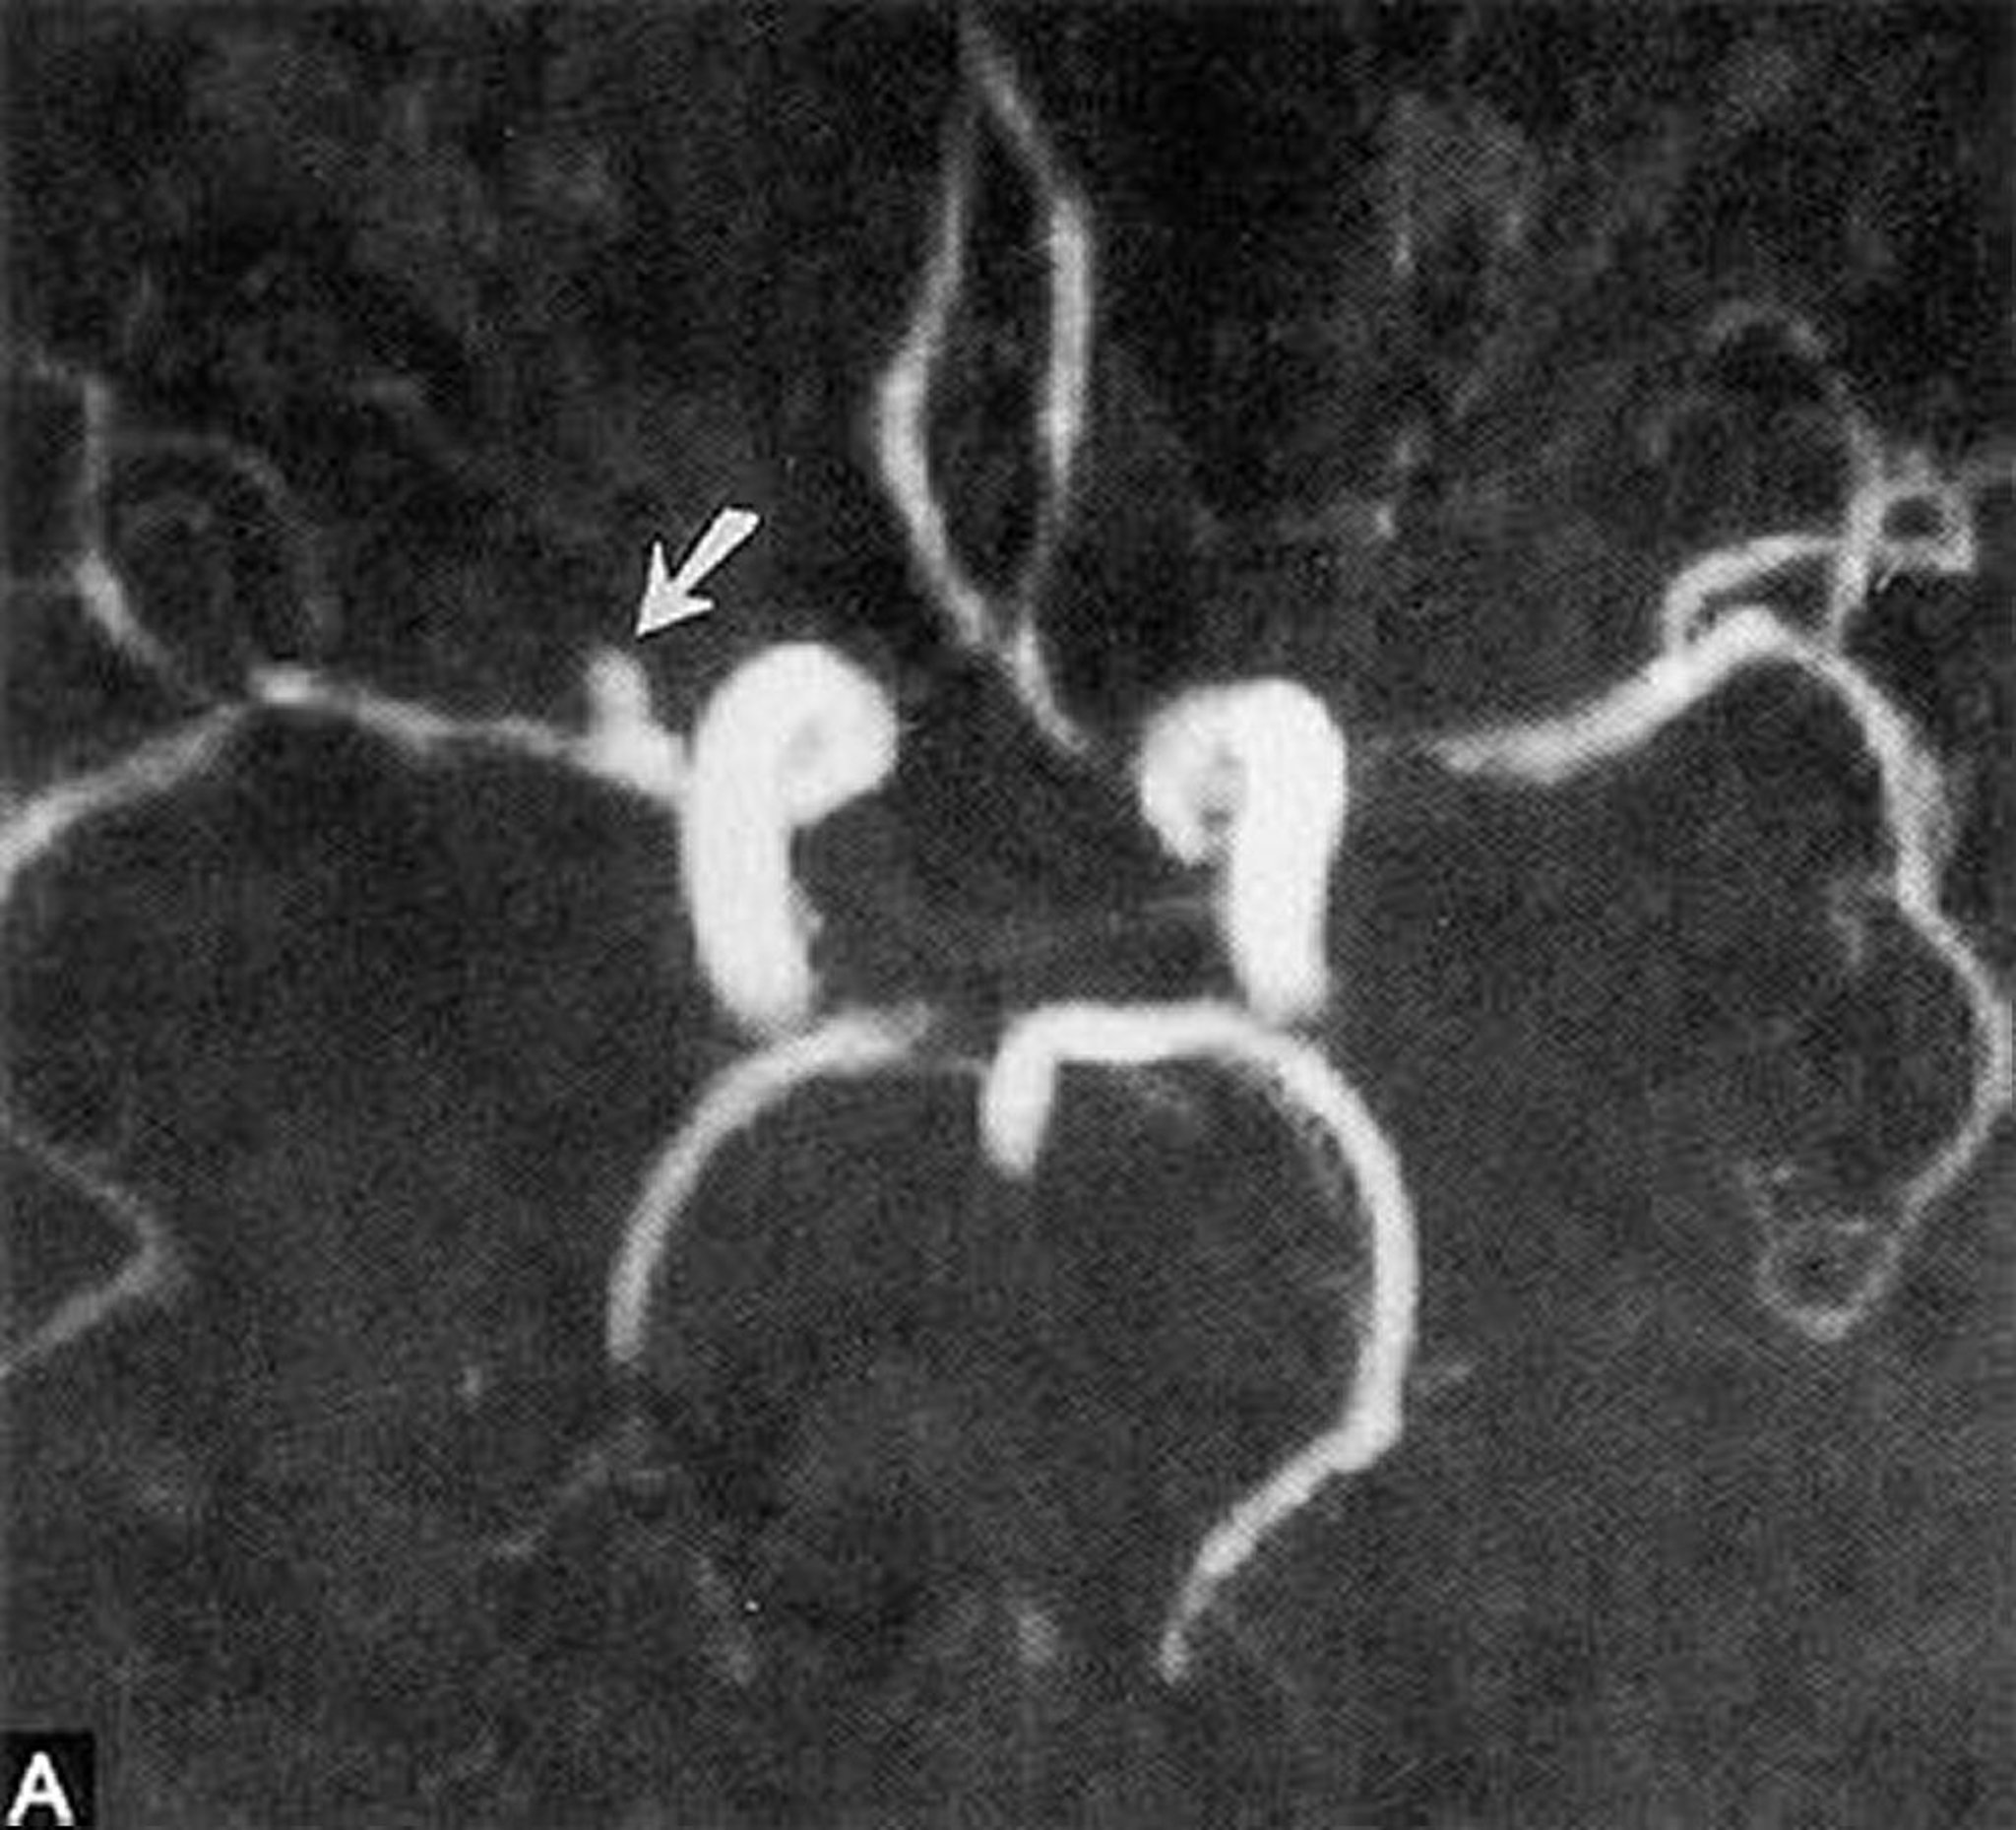

Anévrisme sacculaire

Cette angio-IRM montre un petit anévrisme sacculaire de l'artère cérébrale moyenne horizontale droite (flèche).

By permission of the publisher. From Ritter A, Hayman L, Charletta D. In Atlas of Cerebrovascular Disease. Edited by PB Gorelick and MA Sloan. Philadelphia, Current Medicine, 1996.